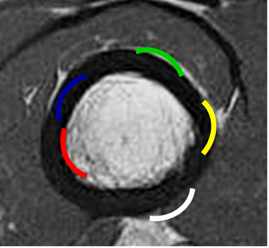

Fig 23. Localización cortical.

RM axial en T1. Zona roja: Lesión endostal. Azul: Intracortical. Amarilla: Subperióstica. Verde: Perióstica y Blanca: Parosteal.